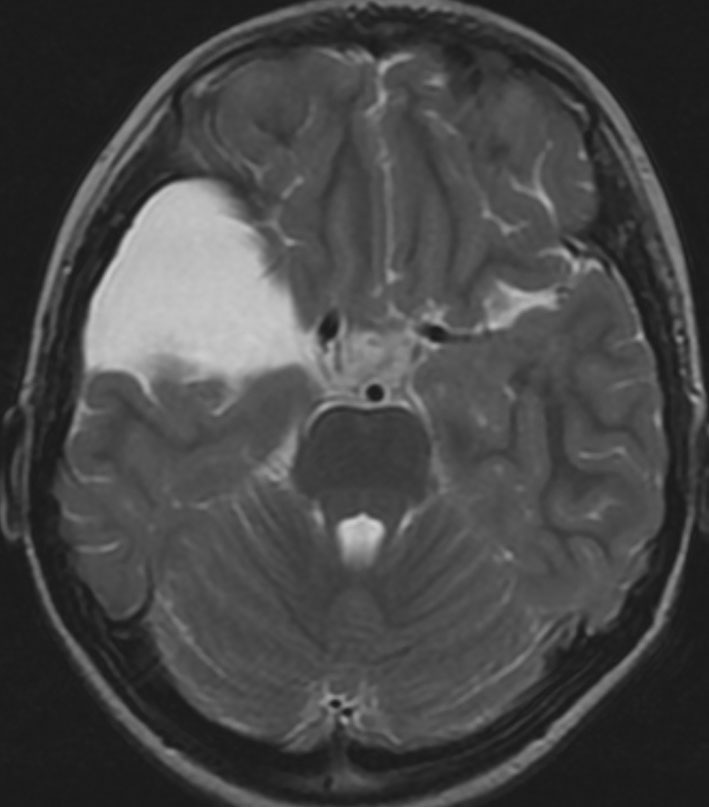

中頭蓋窩・症候性・くも膜のう胞

60代の女性で偶然発見された大きなクモ膜のう胞です。経過とともに少しづつ増大して,ふらつき,眠気,気分の落ち込みなど抑うつ状態となりました。抗うつ薬の投与が開始され増量されましたが精神症状は悪化して何もできなくなりました。おそらく右側頭葉症状として抑うつ症です。内視鏡ですと脳に損傷が生じますから,開頭顕微鏡手術で,クモ膜のう胞を脳底槽へ開窓しました。術後に症状は消失して5年になりますが,抗うつ薬なしで元気にしています。

もしかするとこれは,巨大な choroidal fissure cystかもしれません。